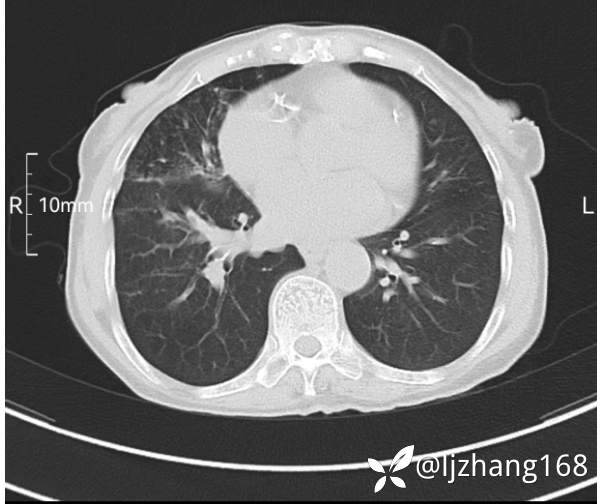

74岁女患,反复咳嗽2月,右肺空洞性病变,炎症OR肿瘤(有病理)

简要病史:2月前开始受凉后出现咳嗽,咳少许白色粘液痰,痰不易咳出,无痰中带血及咯血,无畏寒发热,外院胸部CT提示右下肺空洞病变,脓肿可能性大,常规抗感染治疗效果不佳。既往否认“糖尿病”等病史,有高血压基础病史,无吸烟史。

辅助检查:胸部CT右肺下叶前基底段结节并空洞

临床诊断:右肺空洞:脓肿?